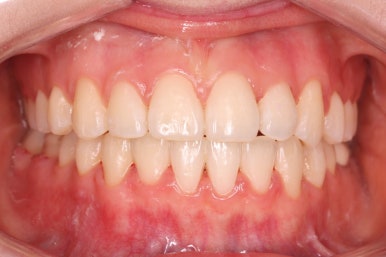

위아랫니가 매우 가지런해졌고 고민하셨던 덧니도 말끔히 개선되었습니다.

또한 비발치, 즉 발치를 안하고 덧니를 가지런하게 했음에도 입이 더 돌출되거나 뻐드러지지 않고 치료를 할 수 있었습니다.

14개월만에 치아는 가지런해졌고, 위아래 치열의 중앙도 맞아졌으며 발치를 하지 않았음에도 치열이 뻐드러지거나 돌출되지 않았습니다.

또한 오히려 부각되었던 대문니의 뻐드러짐이 치료 후 개선이 되었고 웃는 모습도 굉장히 예뻐졌습니다.